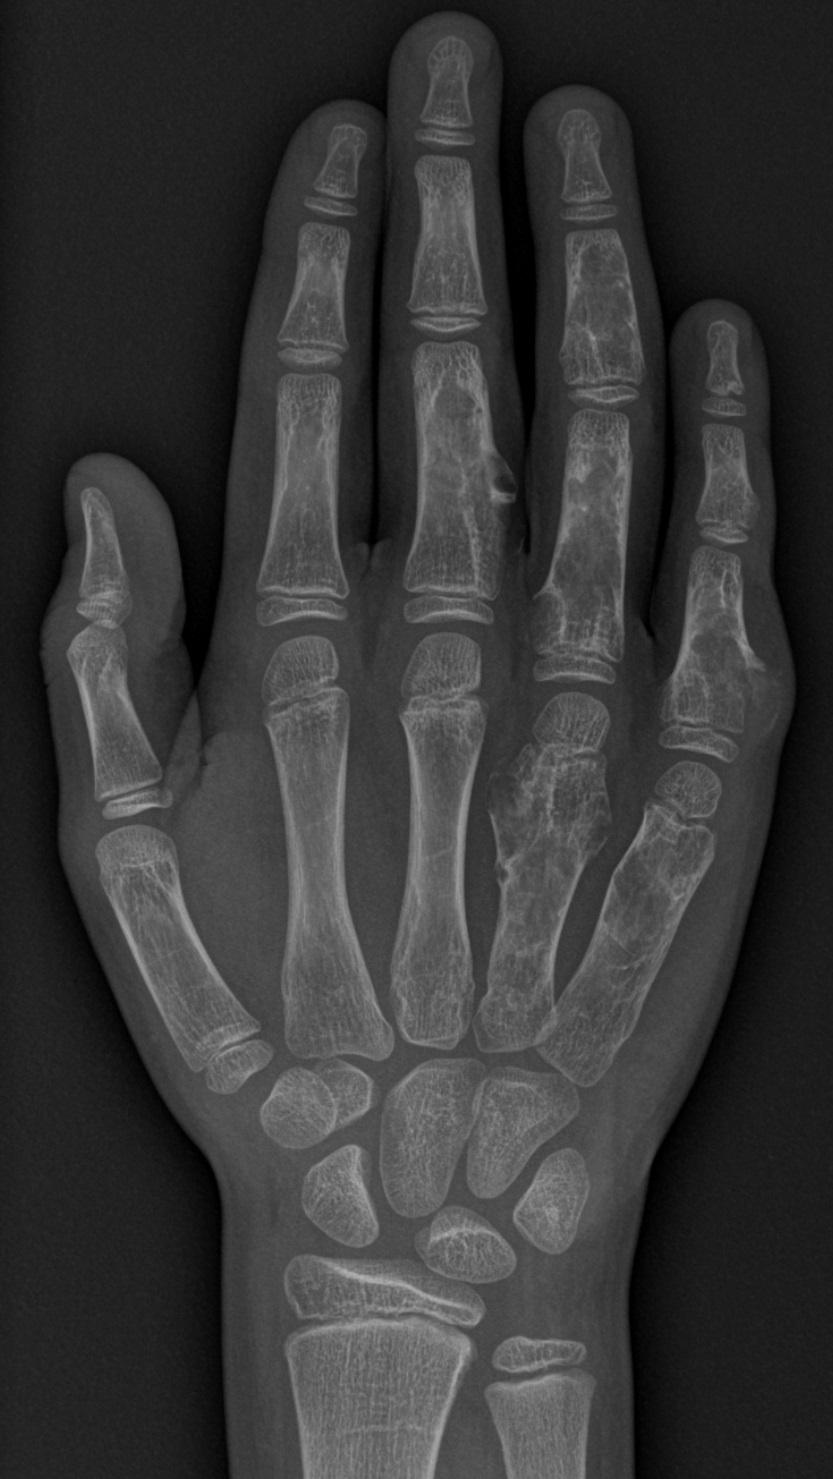

Een 10-jarige jongen had aan zijn vingers beenharde zwellingen die langzaam groeiden. De zwellingen deden geen pijn en hij had recent geen trauma of fractuur doorgemaakt. Op de MRI-scan van de hand waren geen hemangiomen of lymfangiomen te zien.